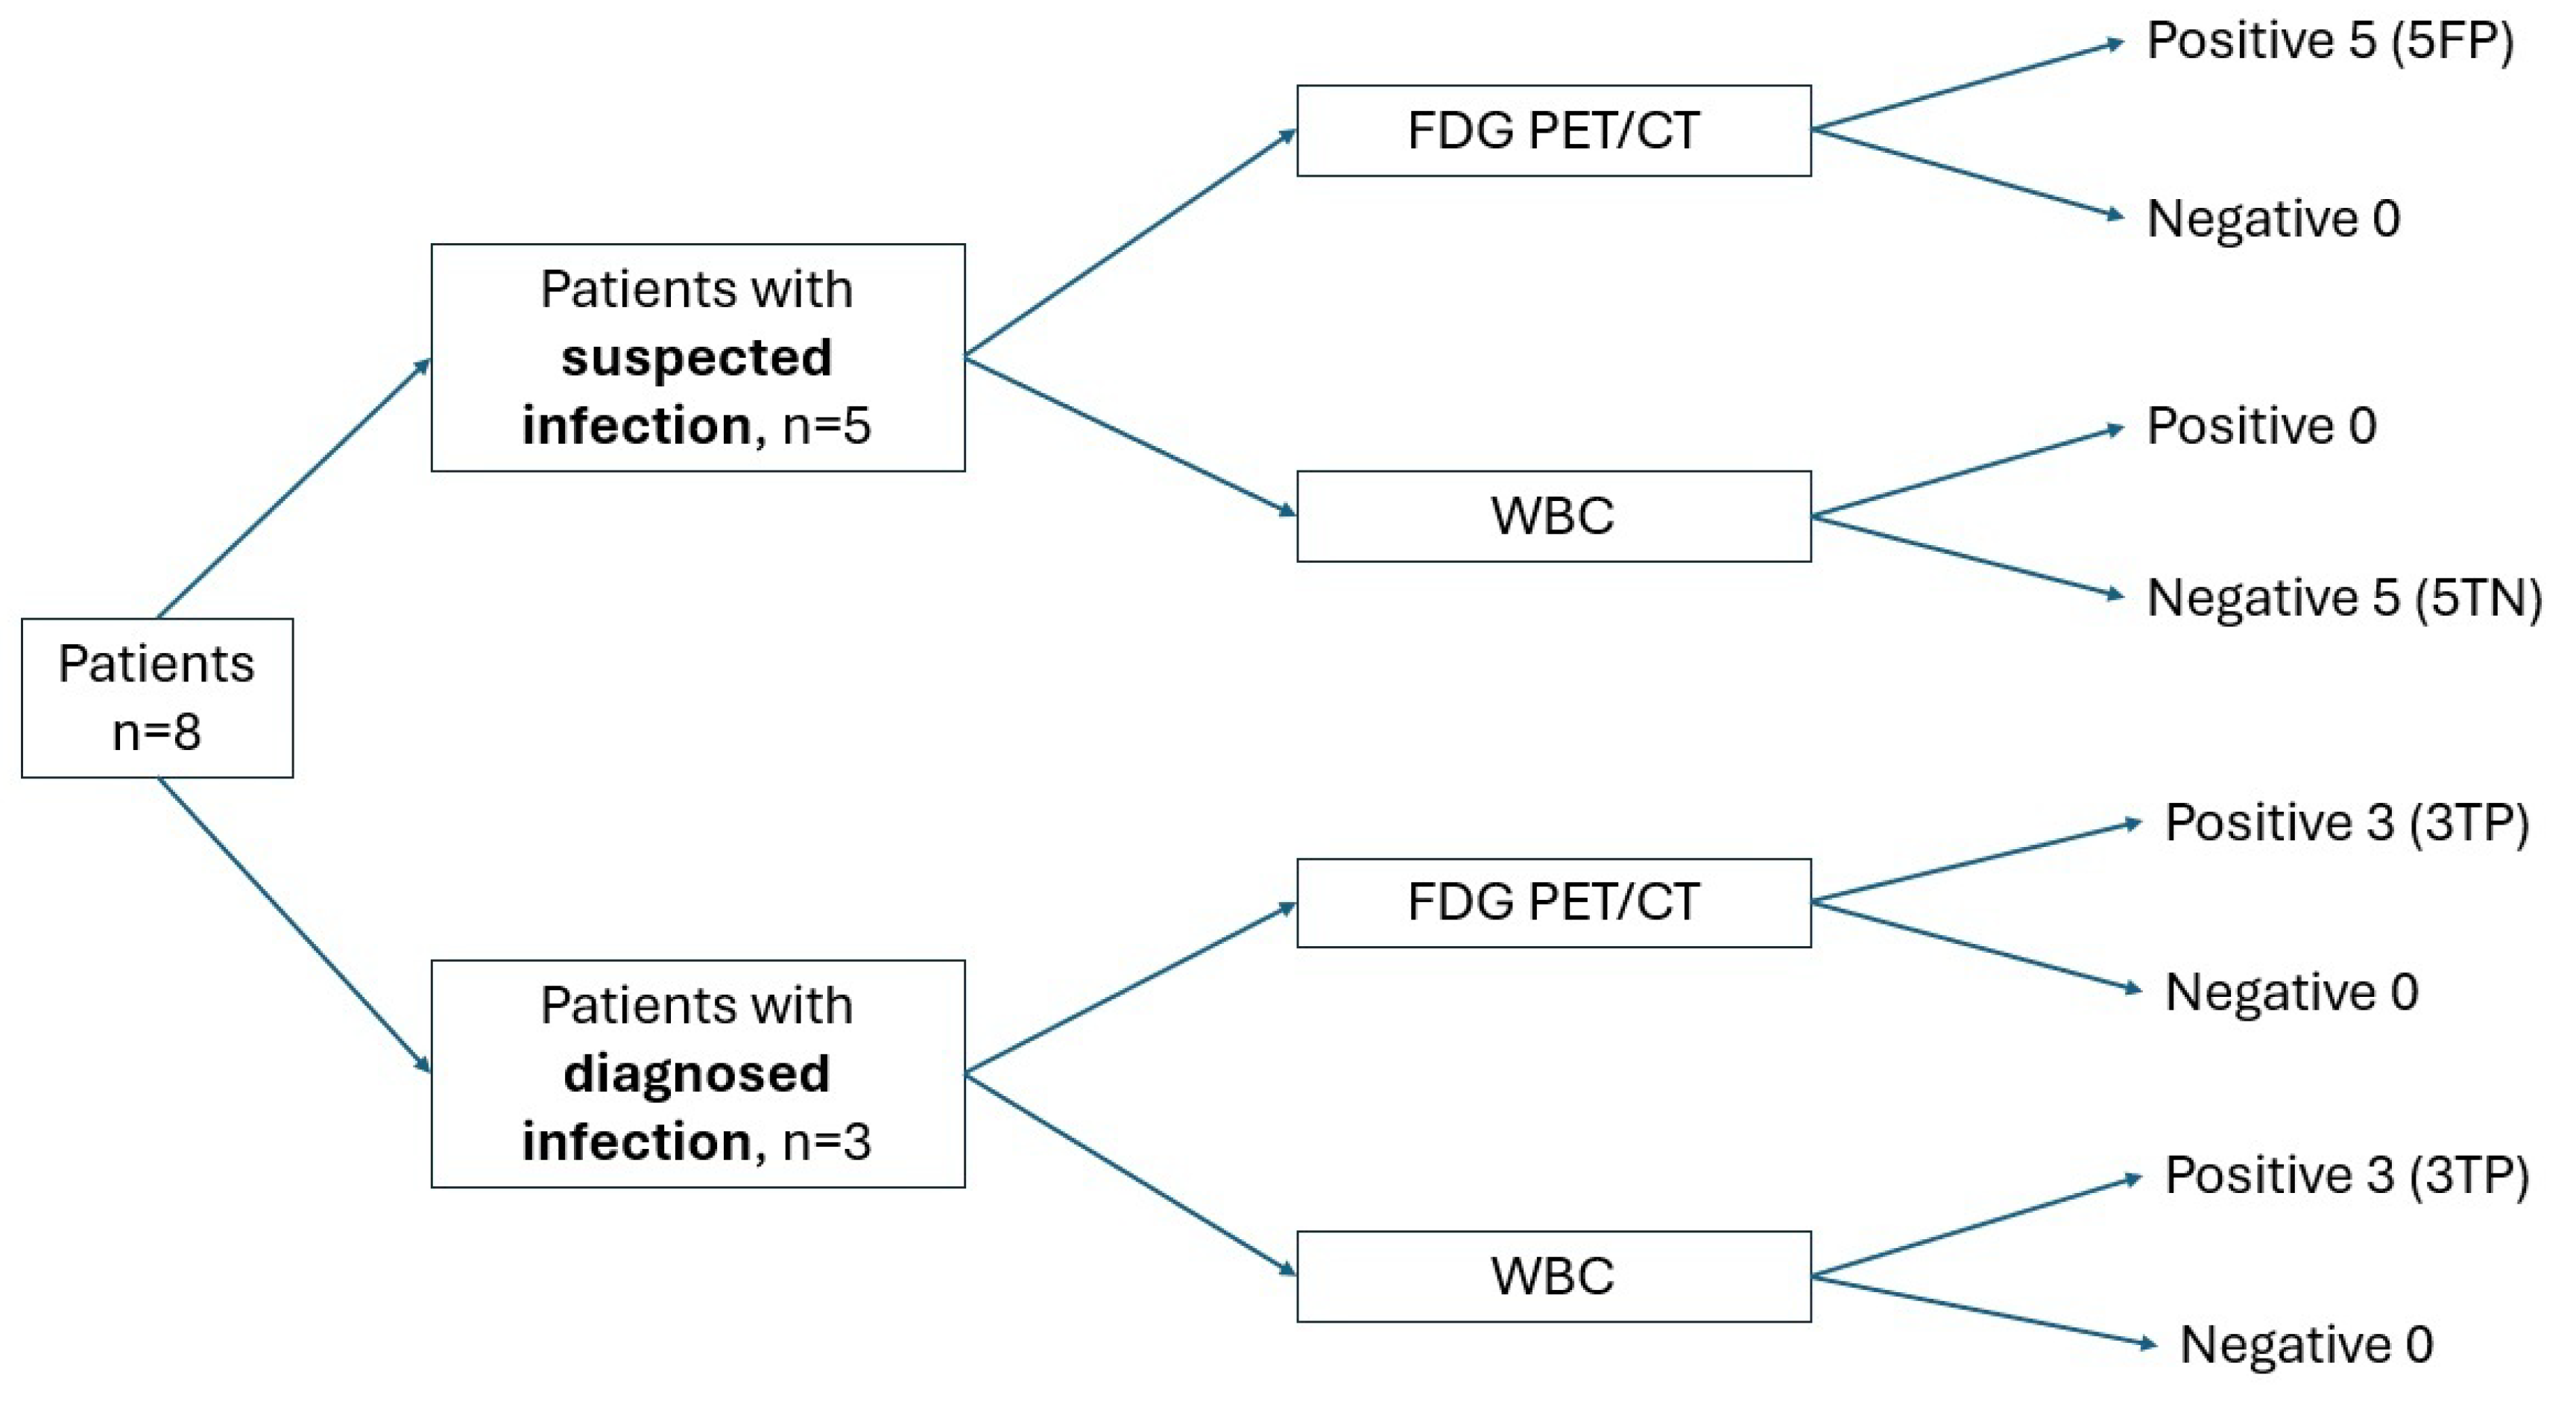

3. Results